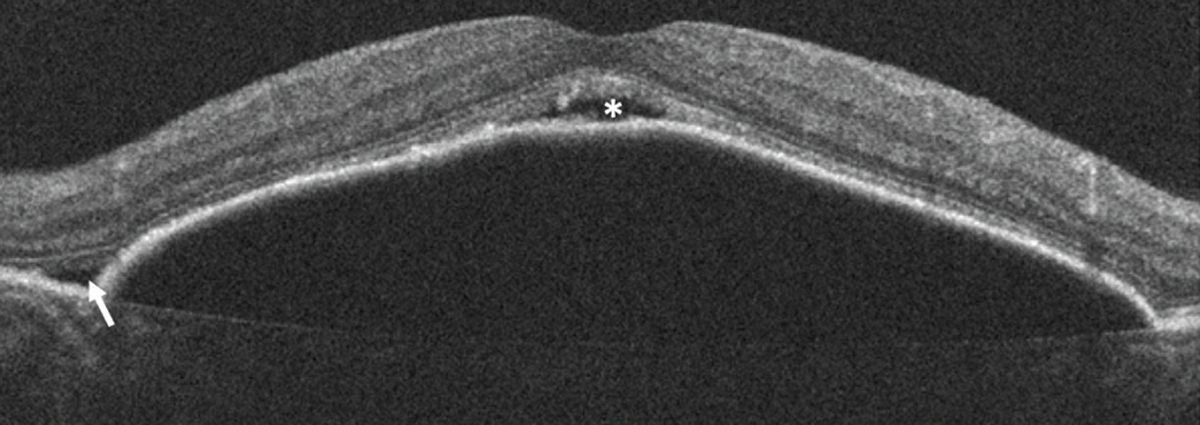

![]() |

| Figure 8. Optical coherence tomography of a large pigment epithelial detachment associated with subretinal fluid at the edge (arrow) and vertex (asterisk) of the PED. |

For example, SRF associated with a PED has been well described in the setting of non-neovascular AMD in a few instances, such as a pocket of fluid along the edge of a PED, at the vertex of a PED or under the retina as it drapes over confluent PEDs (Figure 8).6 Unlike active exudate from a neovascular lesion, this fluid can be thought of as a transudate resulting from RPE dysfunction, due to relative ischemia of the RPE, as it is displaced from the underlying choriocapillaris.6,7 It’s important to identify this as nonexudative to avoid unnecessary treatment.